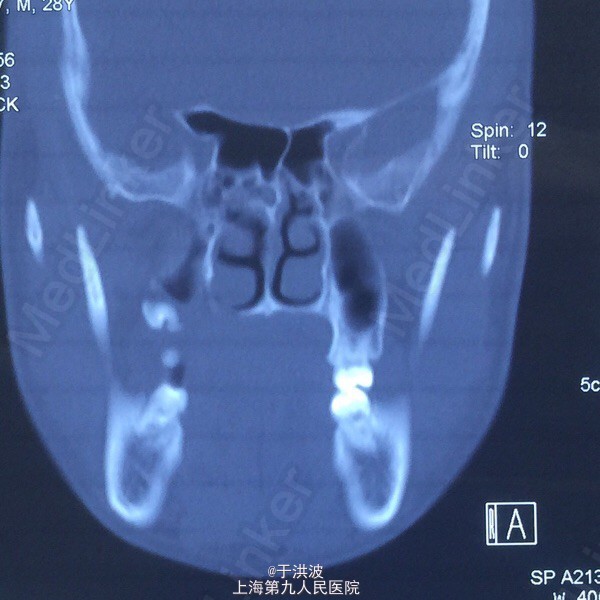

面部基本对称,右侧面部无明显膨胧,无压痛。口内右侧上颌前庭沟黏膜无异常,右侧上颌牙列松动,牙列上移,与下颌牙无咬合接触。CT示右侧上颌骨弥散性吸收。血常规未见异常

右侧上颌骨骨巨细胞瘤?坏死性肉芽肿? 局麻下行切取活检术